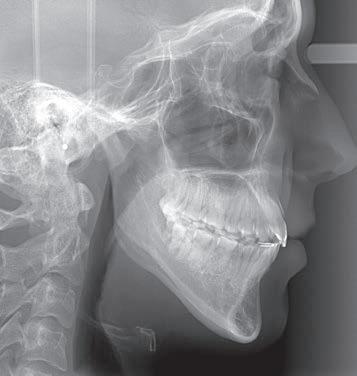

Figs. 7a–f: Final situation achieved after 14 months of treatment (3 months of Motion sagittal treatment and 11 months of Carriere SLX fixed appliance therapy). Intraoral view (a–c); patient’s face (d); cephalometric X-ray (e); pantomograph X-ray (f).

14 months: Sagittal and fixed appliance treatment complete

With 3 months of sagittal treatment and 11 months of fixed appliance treatment, the case finished to a satisfactory result. The final cephalometric and pantomographic X-rays highlight the positioning and health of the roots, a positive sign of the respectful approach of these appliances on the periodontium.

Figs. 15a–g: Comparison of pre- and post-treatment situations. Cephalometric X-rays: initial situation (a); after 3 months of correction – Class I achieved (b); final result (c). Patient’s facial lateral view: initial situation (d); comparation of pre- and post-treatment situations (e). Post-treatment intraoral situation: buccal view lower forward movement (f); central view lower forward movement (g).